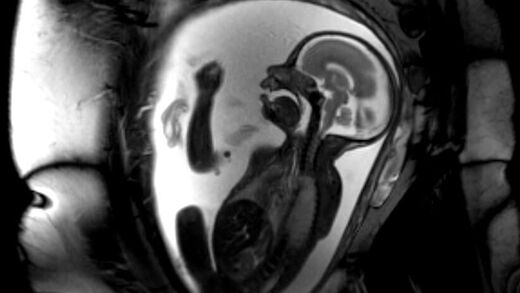

Darüber hinaus zeichnen wir uns in der Neuroradiologie Heidelberg durch eine hohe Expertise in den Spezialverfahren Dental-MRT, einer strahlungsfreien Untersuchung der Zähne, dem Fetalen MRT, also einer strahlungsfreien Untersuchung des ungeborenen Lebens, sowie der MR-Neurographie, einer Untersuchung der peripheren Nerven, aus.